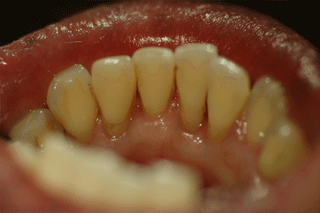

たばこのヤニのついた歯へのPMTCの施術例

PMTC施術前   PMTC施術後

ヤニや歯石がたくさんついています

スケーラーやジェットポリッシャーで汚れを落とします。